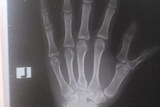

Здравствуйте. У моей дочки на двух ручках по одному дополнительному большому пальцу. Мы делали снимки и дуплес, чтобы врачи определили как лучше удалить лишние пальцы и не использовать гипс и металические конструкции. Теперь одни врачи нам говорят, что никаких проблем нет и можно удалить и всё. А вторые настаивают после удаления закрепить оставшийся палец металлической конструкцией (что-то вроде, как мне объяснили, вставят металлический прут) и использовать гипс, т.к. может быть смещение пальца, но в итоге рабочим пальцы будут на 70%.

Снимки и результаты дуплес прилагаю.

На правой руке палец растет как добавочный, он не деформирует сустав и его возможно удалить без дополнительных конструкций. На левой руке дополнительный палец соединяется в одном суставе с основным и, возможно, придется реконструировать и закреплять сустав.

Если Вы хотите пройти заочную консультацию или операцию у ортопедов в Израиле, перешлите более четкие снимки, а лучше диск, чтобы получить четкий ответ по виду и цене операции.